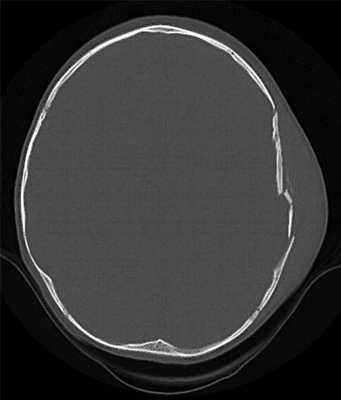

КТ позволяет последовательно изучить мягкие ткани головы, кости черепа, вещество мозга, эпидуральные, субдуральные, субарахноидальные пространства, цистерны основания и желудочки мозга:

- выявить переломы свода и основания черепа (с чувствительностью, намного превышающей традиционную рентгенографию) ,